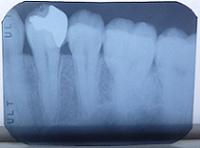

デンタルエックス線写真

縦2㎝×横3㎝くらいの小さなレントゲンです。非常に鮮明なもので、歯周病による骨の吸収だけでなく、ほんの小さな虫歯や歯石、根の病巣などを判別することができます。

視診(見ため)で根の先まで見ることができず病変があるとはわかりません。しかしエックス線写真を見てみると黒く映っている部分(点枠内)に病変があることがわかります。

虫歯

エツクス線で見てみると歯の根っこに大きな虫歯があるのがわかります。